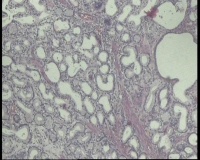

镜下见十二指肠粘液腺明显增多,排列密集,中心有少量平滑肌组织间隔,局灶腺体扩张,是十二指肠息肉还是报十二指肠腺腺瘤?

图1